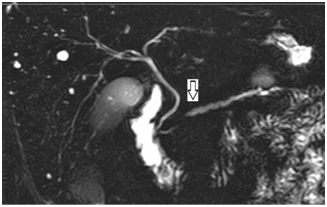

45-year-old man with no medical or surgical history, no alcohol or tobacco consumption, no known allergies or family medical history. With history of abdominal pain in the upper abdomen for about one year. Since one month ago referring with greater intensity in the left hypochondrium. The day of the consult pain intensifies up to 8/10 VAS with irradiation to the back. It was not associated with nausea, vomiting or jaundice. Patient was evaluated at the emergency department where he was found hemodynamically stable, afebrile, without jaundice, with no signs of peritoneal irritation and with diminished bowel sounds. Initial laboratory tests: hematocrit 42%, hemoglobin 14gr/dl, leukocytes 9000/uL, platelets 245000/uL, CRP 12mg/dl, AST 16 IU/ml, (35) ALT 27 IU/ml (50), ALP 65 IU/ml (70), GGT 28 IU/ml, total bilirubin 0.4mg/dl (1), Lipase 2744 U/L, Amylase 204 U/L. An abdominal CT scan was performed which showed peripancreatic edema and inflammatory changes of the peripancreatic adipose tissue (Figure 1). After initial study, mild acute pancreatitis was diagnosed. Biliary etiology was ruled out with an abdominal echotomography that showed a distended gallbladder with no stones, intra- and extra hepatic thin biliary tract. He had no drug or alcohol consumption and triglycerides were in normal range. Abdominal MRI showed a dilated pancreatic duct of 5mm, prominent pancreas and amputation of the pancreatic duct, without evidence of solid or cystic pancreatic lesion (Figure 2). Additional laboratory tests Ca19-9and serum IgG4 were within the normal ranges.

Figure 1 CT: peripancreatic edema.